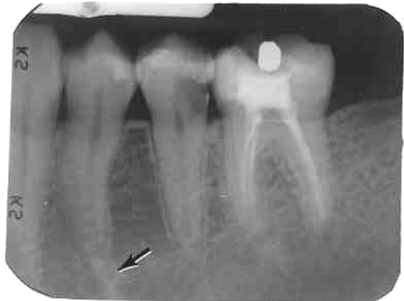

1. What is the anatomical structure indicated by the arrow in this radiograph?